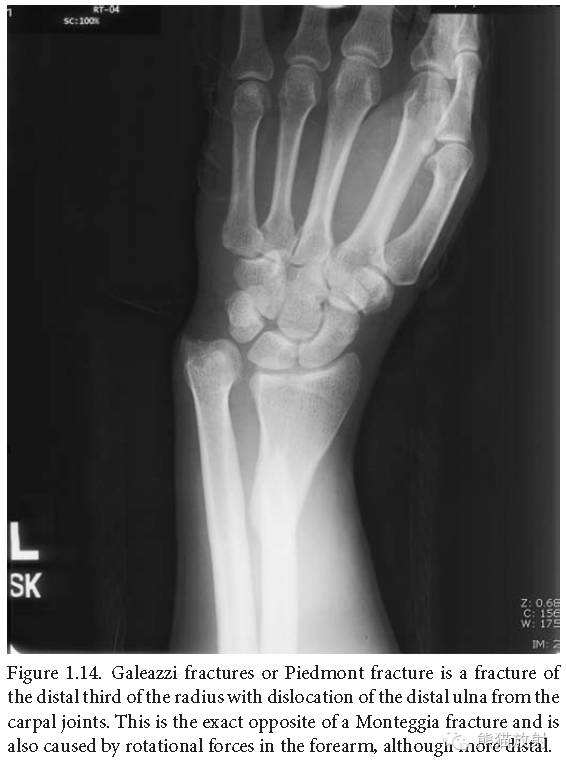

盖氏骨折:桡骨中下1/3骨折合并下尺桡关节脱位;与孟氏骨折完全相反,也是由前臂旋转暴力所致,但较孟氏骨折更为常见。

盖氏骨折:在正位片上常被误认为简单的桡骨远段骨折,在侧位片上脱位显示的更加明显。